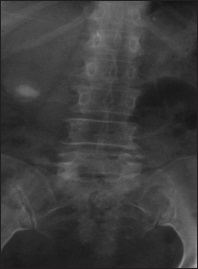

Emphysematous cystitis, radiological diagnosis

Dr. Nelson Chukwuemeka Nwankwo, Cecils Obinna Maduforo (Author)

23-25